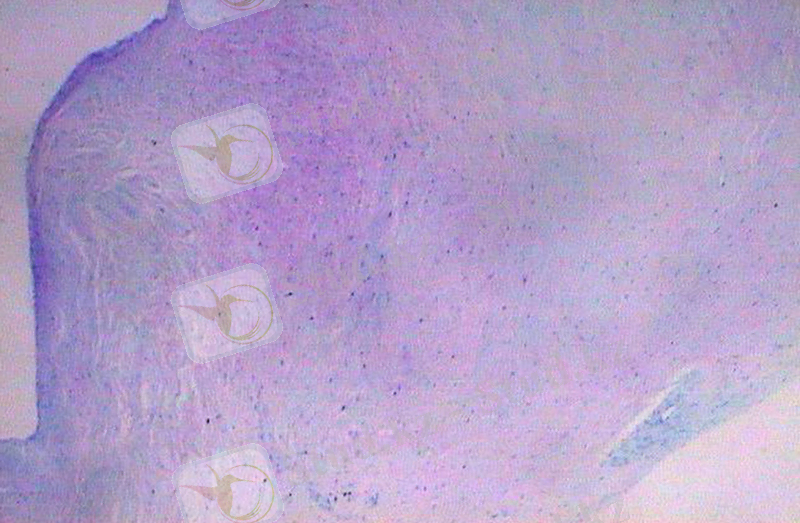

4 сурет. Бүйрек амилоидозы

Амилоидоз - дәнекер ұлпада және қан тамырлар қабырғасында аномалді белок - амилоидтың пайда болуымен сипатталады. Амилоид құрамында организмге бөтен, тән емес фибрилярлы белок бар. Оны амилоидобластар түзеді.

Амилоидоз: жүйелік және жергілікті сипатта кездеседі. Жалпы немесе жүйелі амилоидоз - әртүрлі мүшелердегі амилоидты массалардың бір мезгілде түзілуі. Ол ұсақ қан тамырларының қабырғаларында, эндотелий астында, сондай-ақ ретикулярлы талшықтардың жүрісінде және бездердің эпителийінің базальды мембранасының астында жиналады. Патология жағдайында дәнекер ұлпаның плазмалық торашалары, фибробластар, ретикулярлы торшалар, Купфер торшалары амилоидобластарға ауысады. Амилоид ұлпада ретикулярлы және коллаген талшықтарын бойлай орналасады. Амилоидозбен жиі бауыр, бүйрек, көк бауыр, ішек, бүйрек үсті бездері зақымдалады.